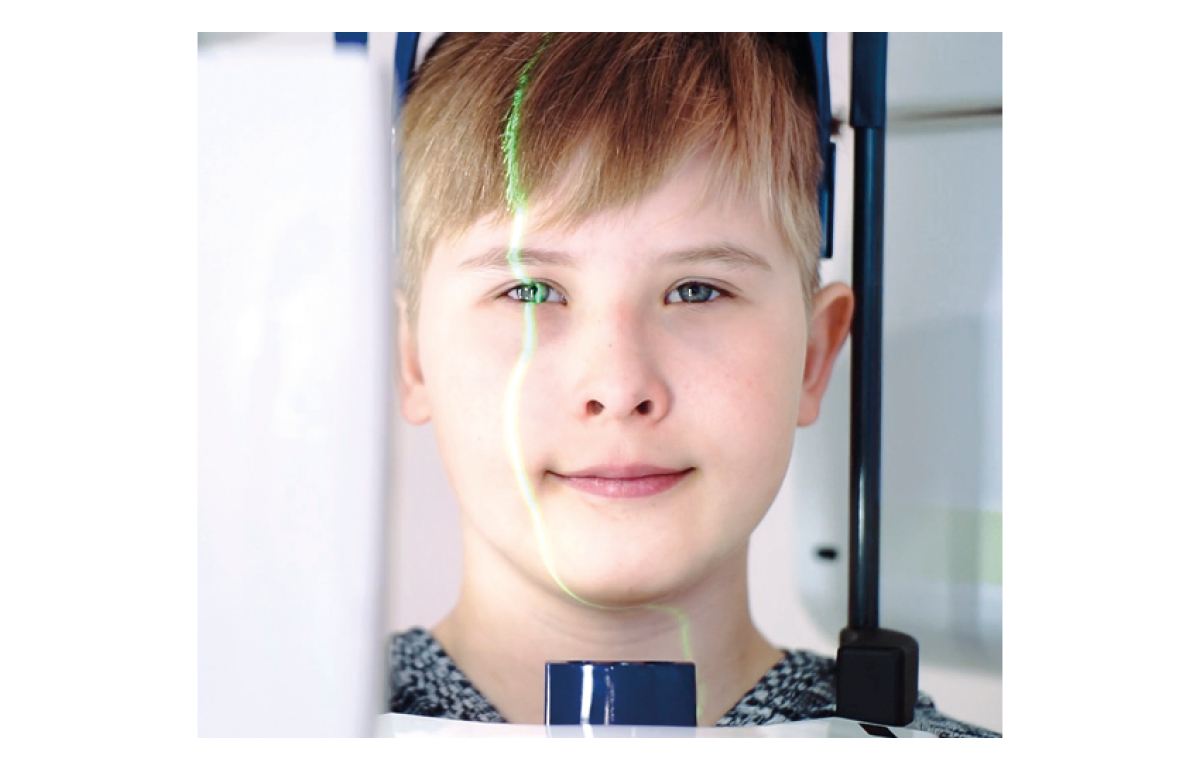

Planmeca ProMax 3D is a product family consisting of exceptional all-in-one units. All Planmeca CBCT units support three different types of 3D dental imaging – as well as panoramic, extraoral bitewing and cephalometric imaging. Planmeca is the first company to combine three different types of 3D data within one X-ray unit, ensuring these intelligent machines meet all maxillofacial imaging requirements. The ProMax family brings together a Cone Beam Computed Tomography (CBCT) image, 3D face photo and 3D model scan into one 3D image – using the same advanced software.

Premium image quality

Packed with intelligent high-tech solutions and algorithms, all Planmeca CBCT units offer an effortless imaging process and crystal-clear images — and at a low dose. These units have been designed to prevent human error with options for correcting movement as well as noise and artefact reduction.